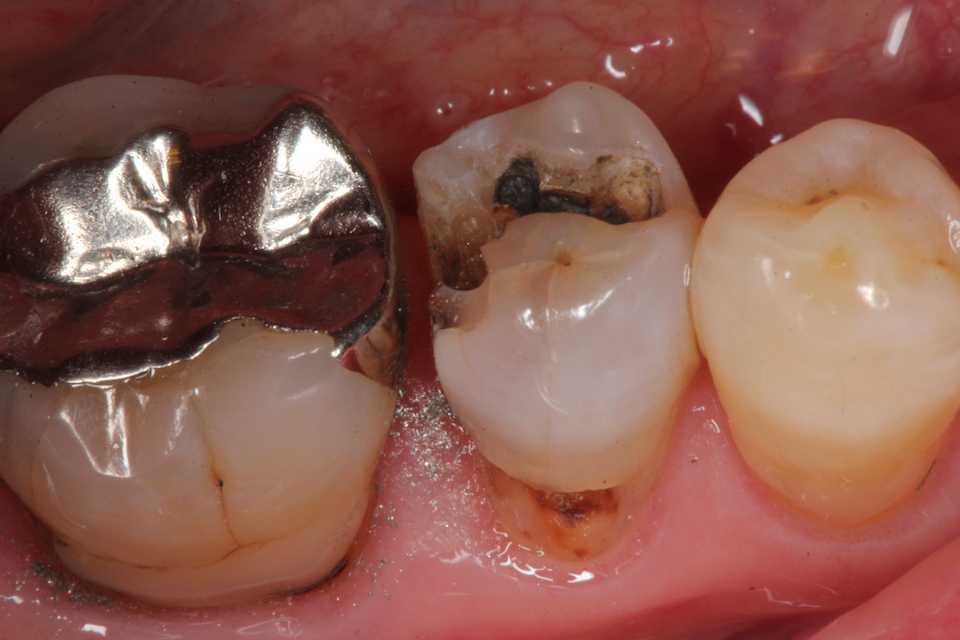

50代女性、右下5、インレー2次カリエス

では時系列でどうぞ